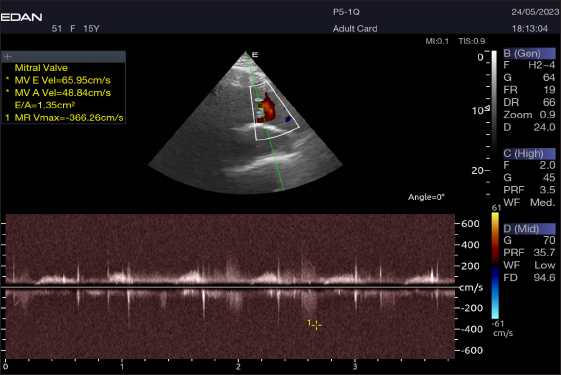

The Mv E/A (Fig. 8), Tv E/A (Fig. 9), and maximum velocity of the aortic valve (Av Vmax) (Fig. 10) were all measured using pulsed-wave Doppler at LPSLAx in all camels. Two cases were observed with mild mitral regurgitation detected through continuous-wave Doppler, but the regurgitation was not considered significant (Fig. 11).

Fig. 8. Left parasternal longitudinal axis of a 16-year-old racing camel showing pulsed wave Doppler over the mitral valve (1=E wave and 2=A wave).

The pulsed-wave Doppler echocardiography of racing camels is not well documented. While all camels had their Mv E/A, Tv E/A, and maximum velocity of the Av Vmax recorded using pulsed-wave Doppler at (LPSLAx), the majority of cases (58.4%) had trouble measuring the pulmonary valve from the right short parasternal view. Using continuous-wave Doppler, minor mitral regurgitation was observed in two patients, but the regurgitation was not substantial.